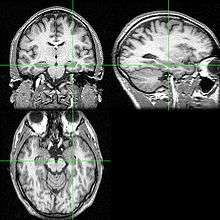

Recent research using neuro-imaging technology including PET and fMRI scanning has shown that there is an extensive amount of distributed brain activation during the process of episodic encoding and retrieval. Among the various regions, the two most active areas during the constructive processes are the medial temporal lobe (including the hippocampus) and the prefrontal cortex.[10] The Medial Temporal lobe is especially vital for encoding novel events in episodic networks, with the Hippocampus acting as one of the central locations that acts to both combine and later separate the various features of an event.[11][12] Most popular research holds that the Hippocampus becomes less important in long term memory functioning after more extensive consolidation of the distinct features present at the time of episode encoding has occurred. In this way long term episodic functioning moves away from the CA3 region of the Hippocampal formation into the neocortex, effectively freeing up the CA3 area for more initial processing.[12] Studies have also consistently linked the activity of the Prefrontal Cortex, especially that which occurs in the right hemisphere, to the process of retrieval.[13] The Prefrontal cortex appears to be utilized for executive functioning primarily for directing the focus of attention during retrieval processing, as well as for setting the appropriate criterion required to find the desired target memory.[10]